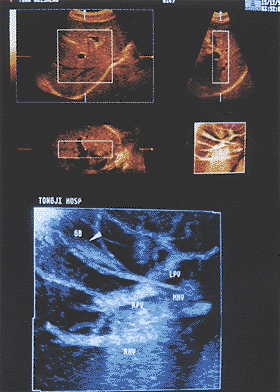

实质性脏器内正常血管的三维图像:用透明成像最小回声模式对20例正常肝内血管进行三维重建的结果显示:正常肝内血管的三维图像可见肝内血管连续性好,各分支间空间关系明确,能显示末端细小的分支或属支,管道走行无迂曲扩张。在整体显示肝内血管方面较二维图像更优越,能显示较二维图像高1~2级的血管分支(图1)。其中1例患者在一幅三维图像内,能同时显示下腔静脉、三支肝静脉、门静脉主干、左右支及分支,最高可显示门静脉的第5级分支,并保持与其上各级分支血管间的连续性,这在一般二维图像上是难以达到的(图2)。对5例正常脾脏血管进行的三维超声重建也可获得类似结果。

GB:胆囊,LPV:门静脉左支,RPV:门静脉右支,MHV:中肝静脉,RHV:右肝静脉

图1 上:正常人肝内血管三个不同断面的二维图像

下:利用透明成像最小回声模式重建的肝内血管三维图像

显示门静脉、肝静脉与下腔静脉的空间位置关系.IVC:下腔静脉,RHV:右肝静脉,MHV:中肝静脉,LHV:

左肝静脉,RPV:门静脉右支,LPV:门静脉左支,MPV:

门静脉主干,箭头处为门静脉左支矢状部